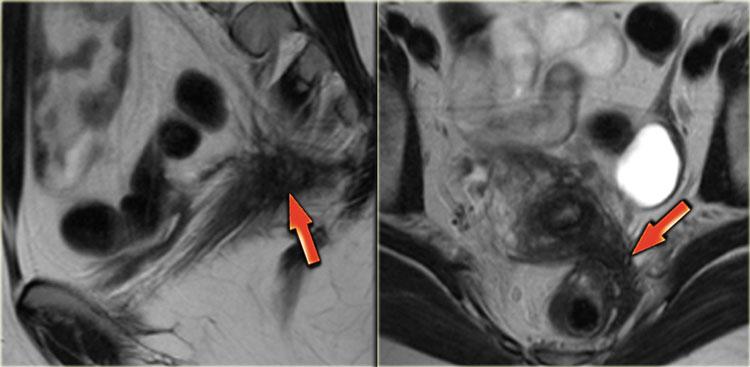

Hình ảnh T2W cho thấy hai tổn thương giảm tín hiệu hình nan quạt (mũi tên đỏ).

Những đặc điểm này điển hình cho các tổn thương lạc nội mạc tử cung xâm lấn lớp cơ thành ruột.

Ngoài ra còn có phù nề dưới niêm mạc, biểu hiện là tăng tín hiệu ở phía lòng ruột của thành ruột.

Các hình ảnh T2W này cho thấy giãn niệu quản đoạn xa bên trái do lạc nội mạc tử cung xâm lấn sâu lan rộng xâm lấn dây chằng tử cung-cùng bên trái, lan đến đại tràng sigma.